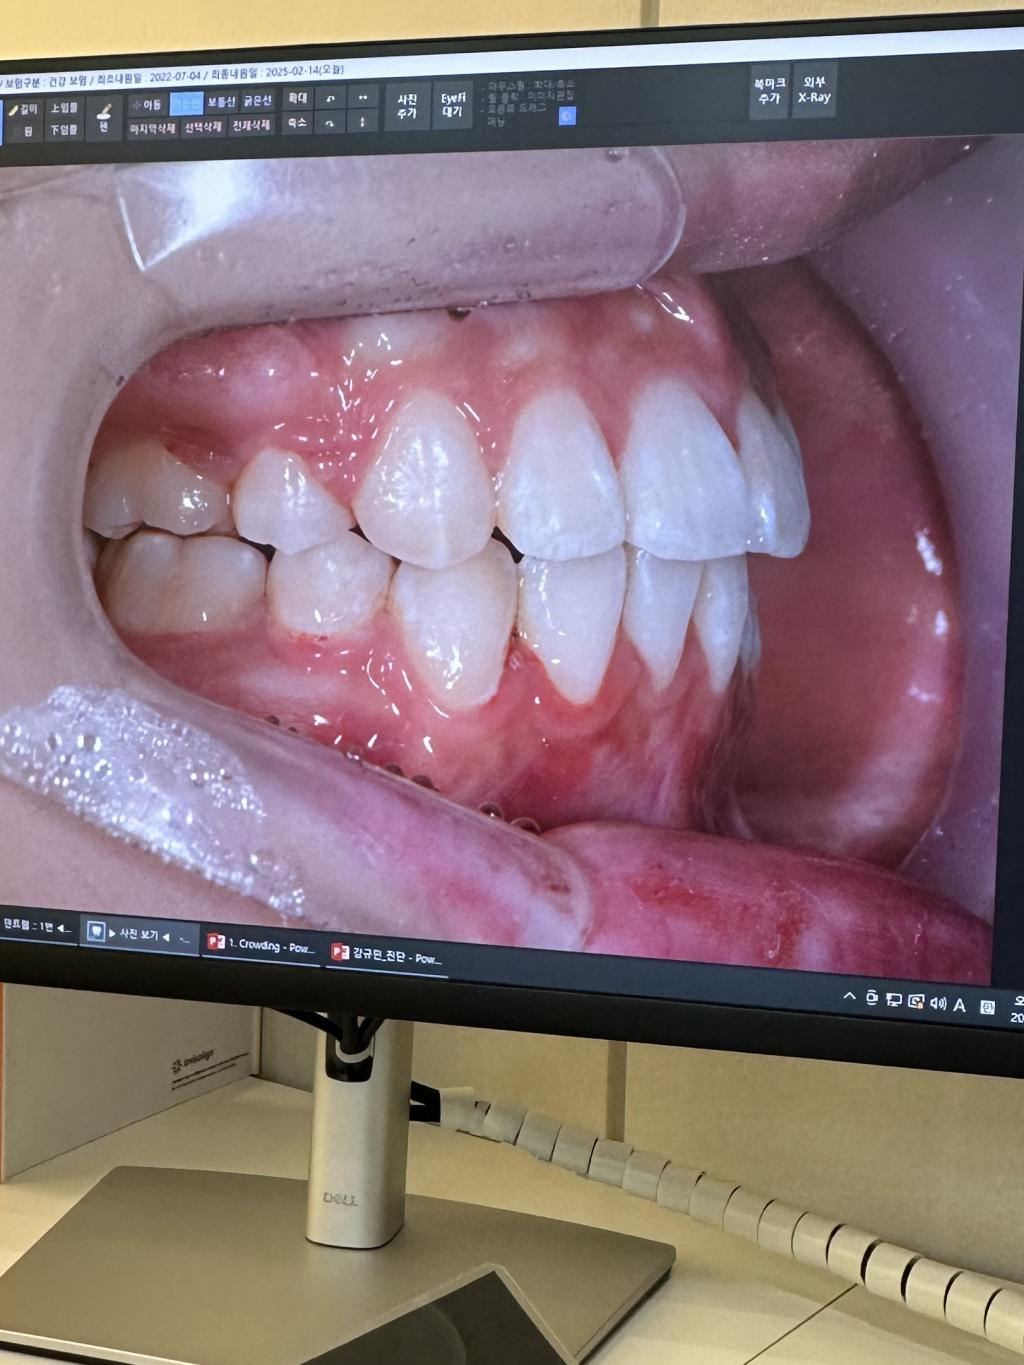

돌출입 치아교정입니다

안녕하세요. 교정을 막 끝낸 23살 여자입니다. 교정과선생님들 답변해주시면 진심으로 감사드리겠습니다..

완료된 사진입니다,, 앞니가 덜 넣은게 맞는거죠.. 더 넣고싶어요..

다른의사분들의 진실한 의견들이 필요합니당 ㅜㅜ